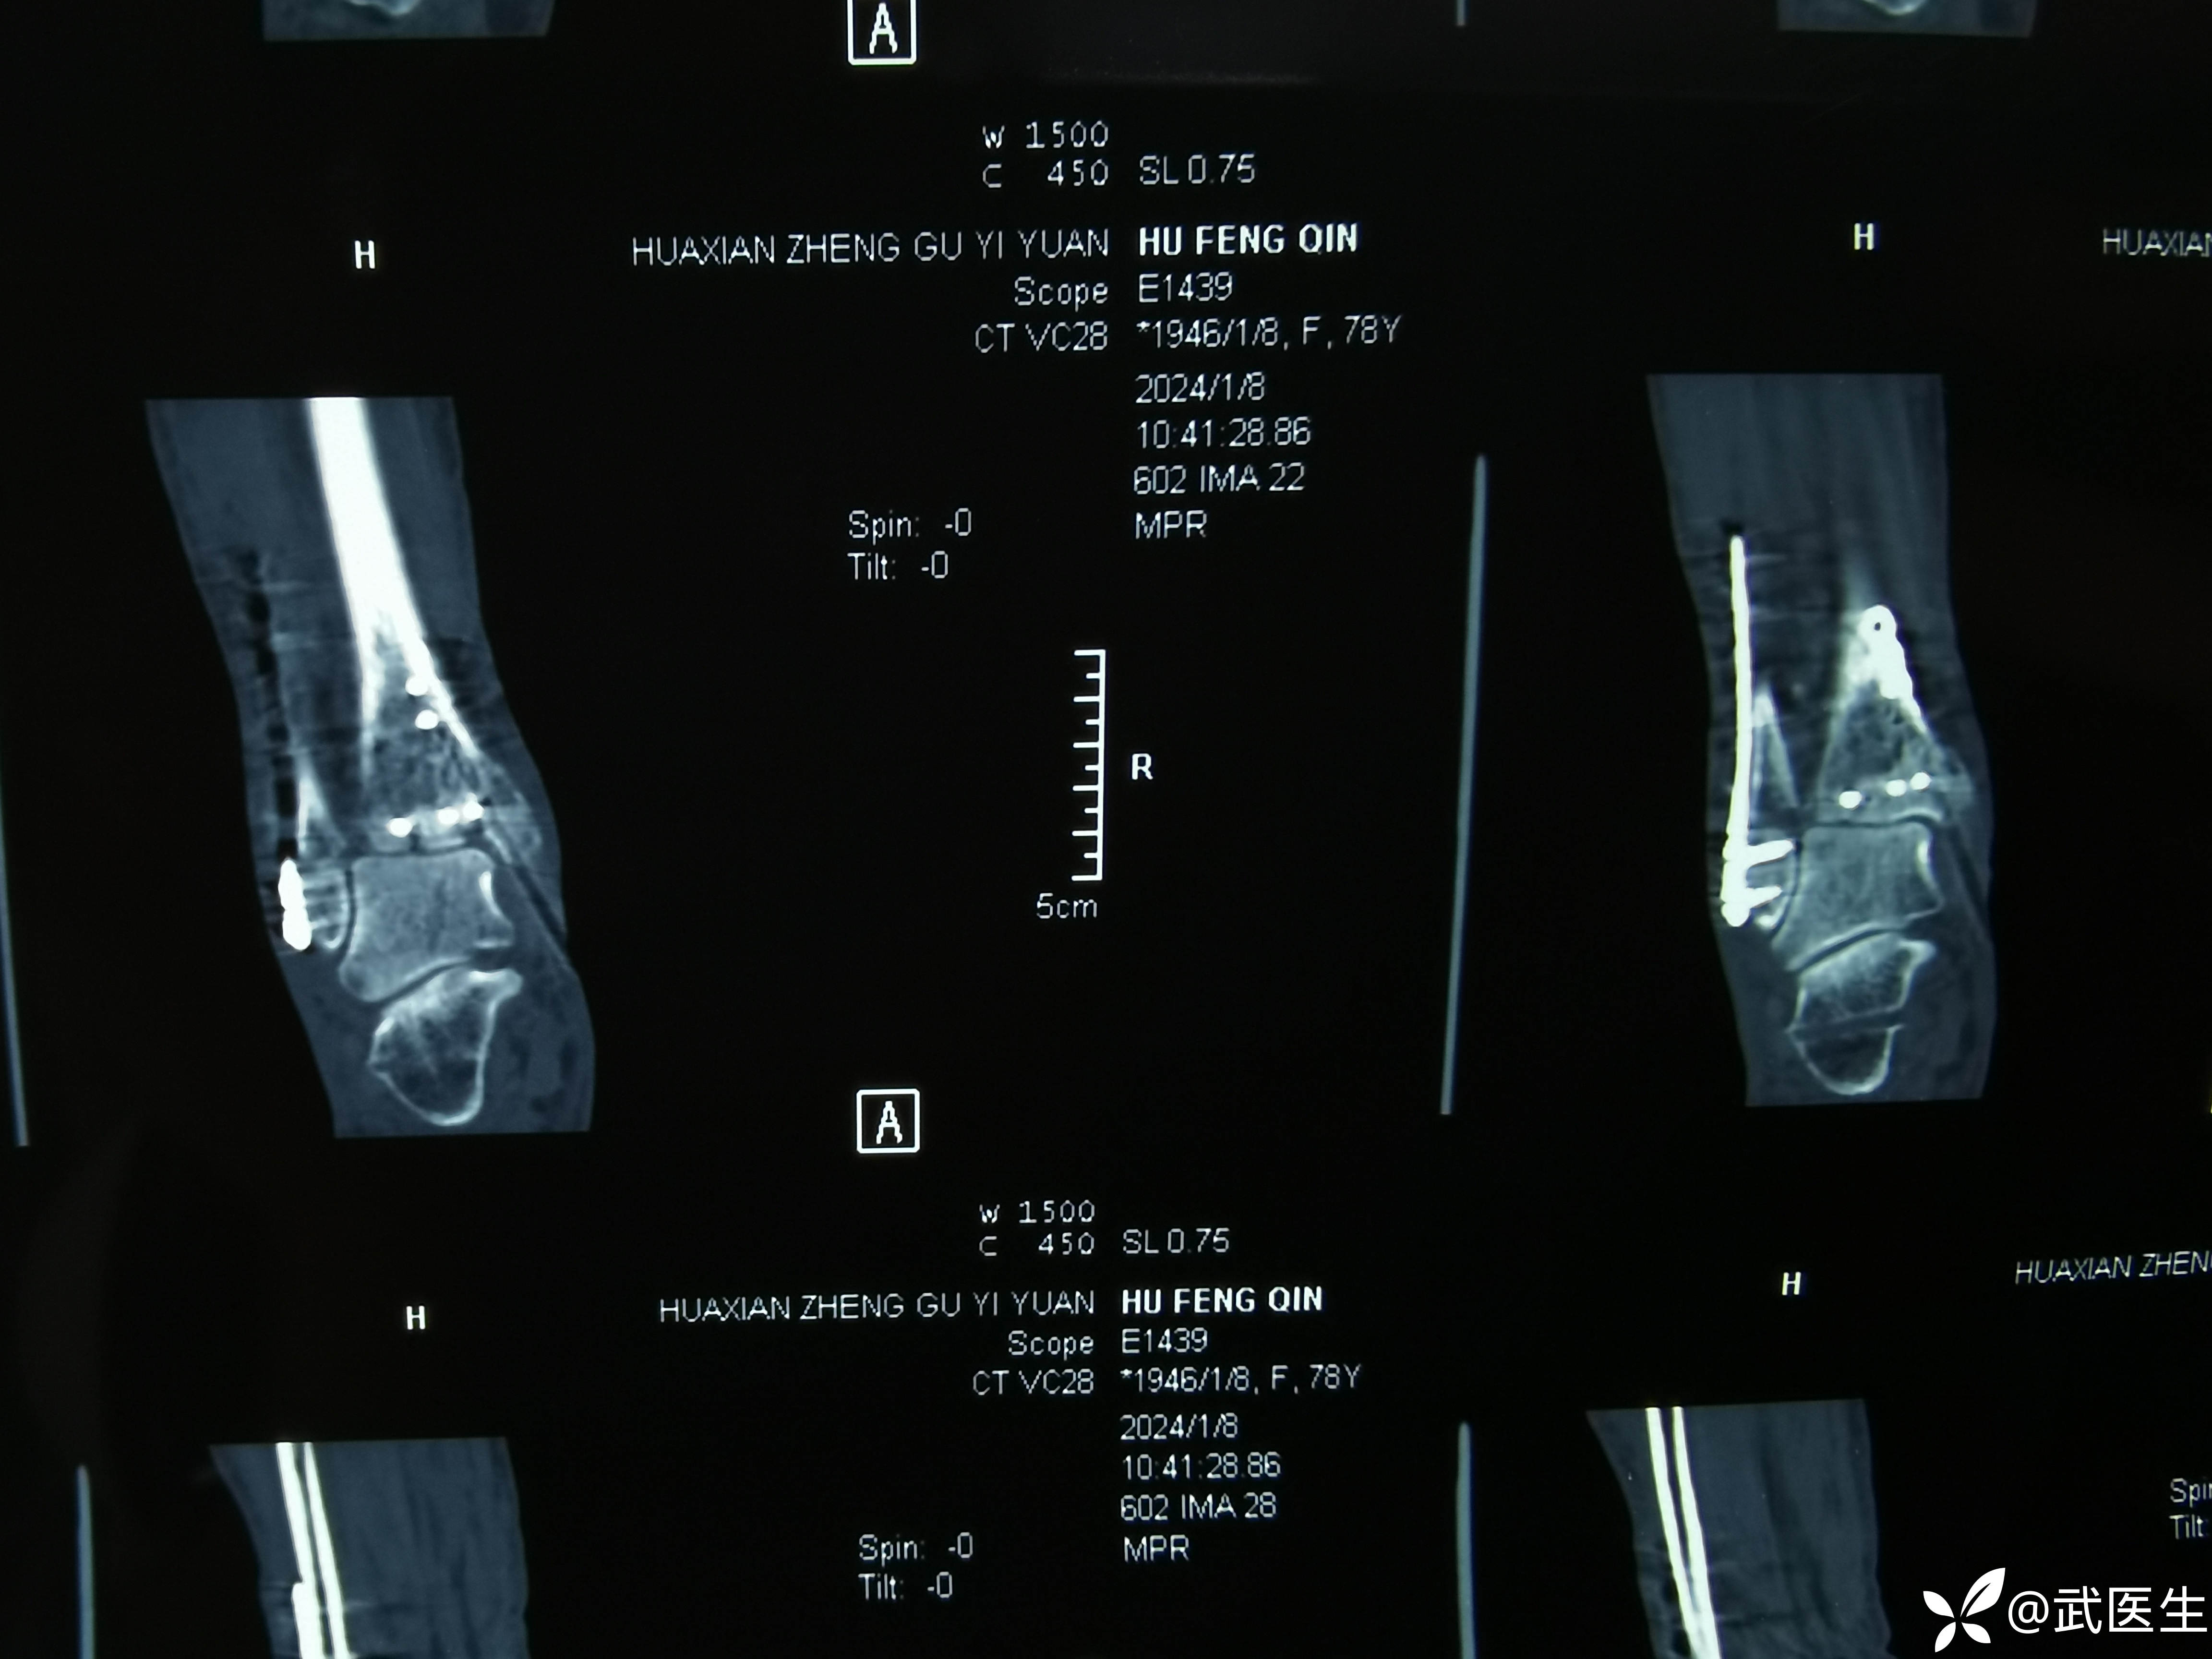

术后ct,复位还行